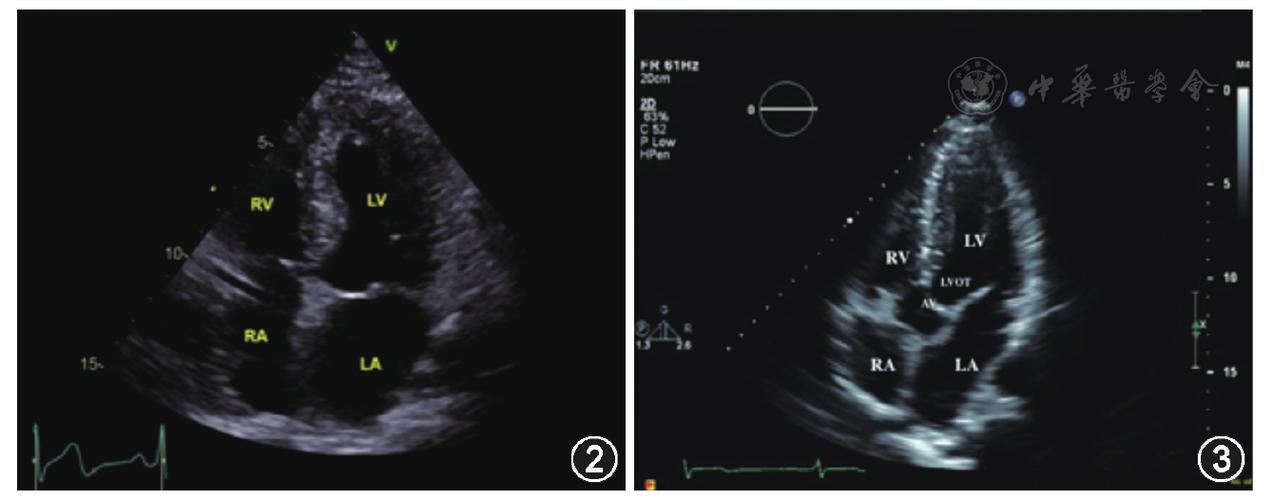

点击查看大图 图2 心尖四腔心切面超声图像 图3 心尖五腔心切面超声